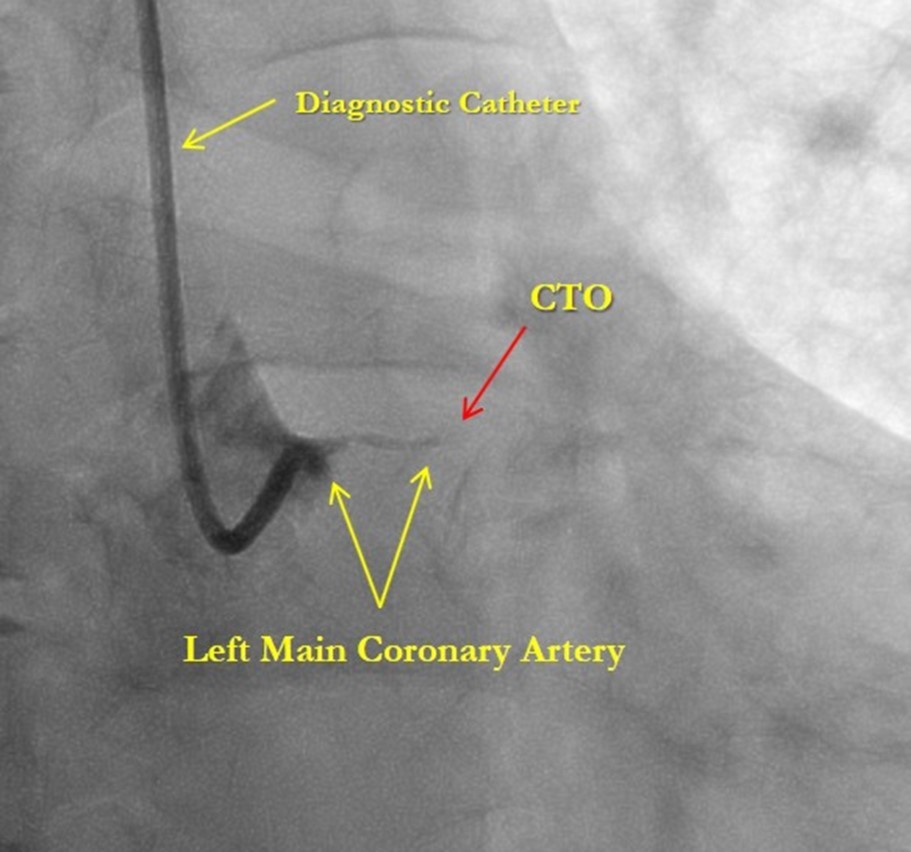

After medical treatment and comparable improvement in the patient's condition, expected risks were re-evaluated. After consulting with the patient and family members (they did not agree to the operation based on past experience) it was resolved to perform repeated CAG and to attempt revascularization of the LAD artery, (stenting). However, repeated CAG additionally revealed chronic 100% occlusion of the LMCA (Figure 1), and also CX occlusion, which was unexpected, and thereby significantly decreasing the likelihood of procedural success. In this case, the patient's heart was supplied only through the right coronary artery, which partially supplies the occluded left anterior descending and circumflex arteries through the contralateral collateral blood flow (Figure 2). Acute LMCA occlusion in most of the cases is fatal and survival is possible only in patients with a dominant RCA providing sufficient collateral formation.

Figure 1.Chronic total occlusion of the left main coronary artery